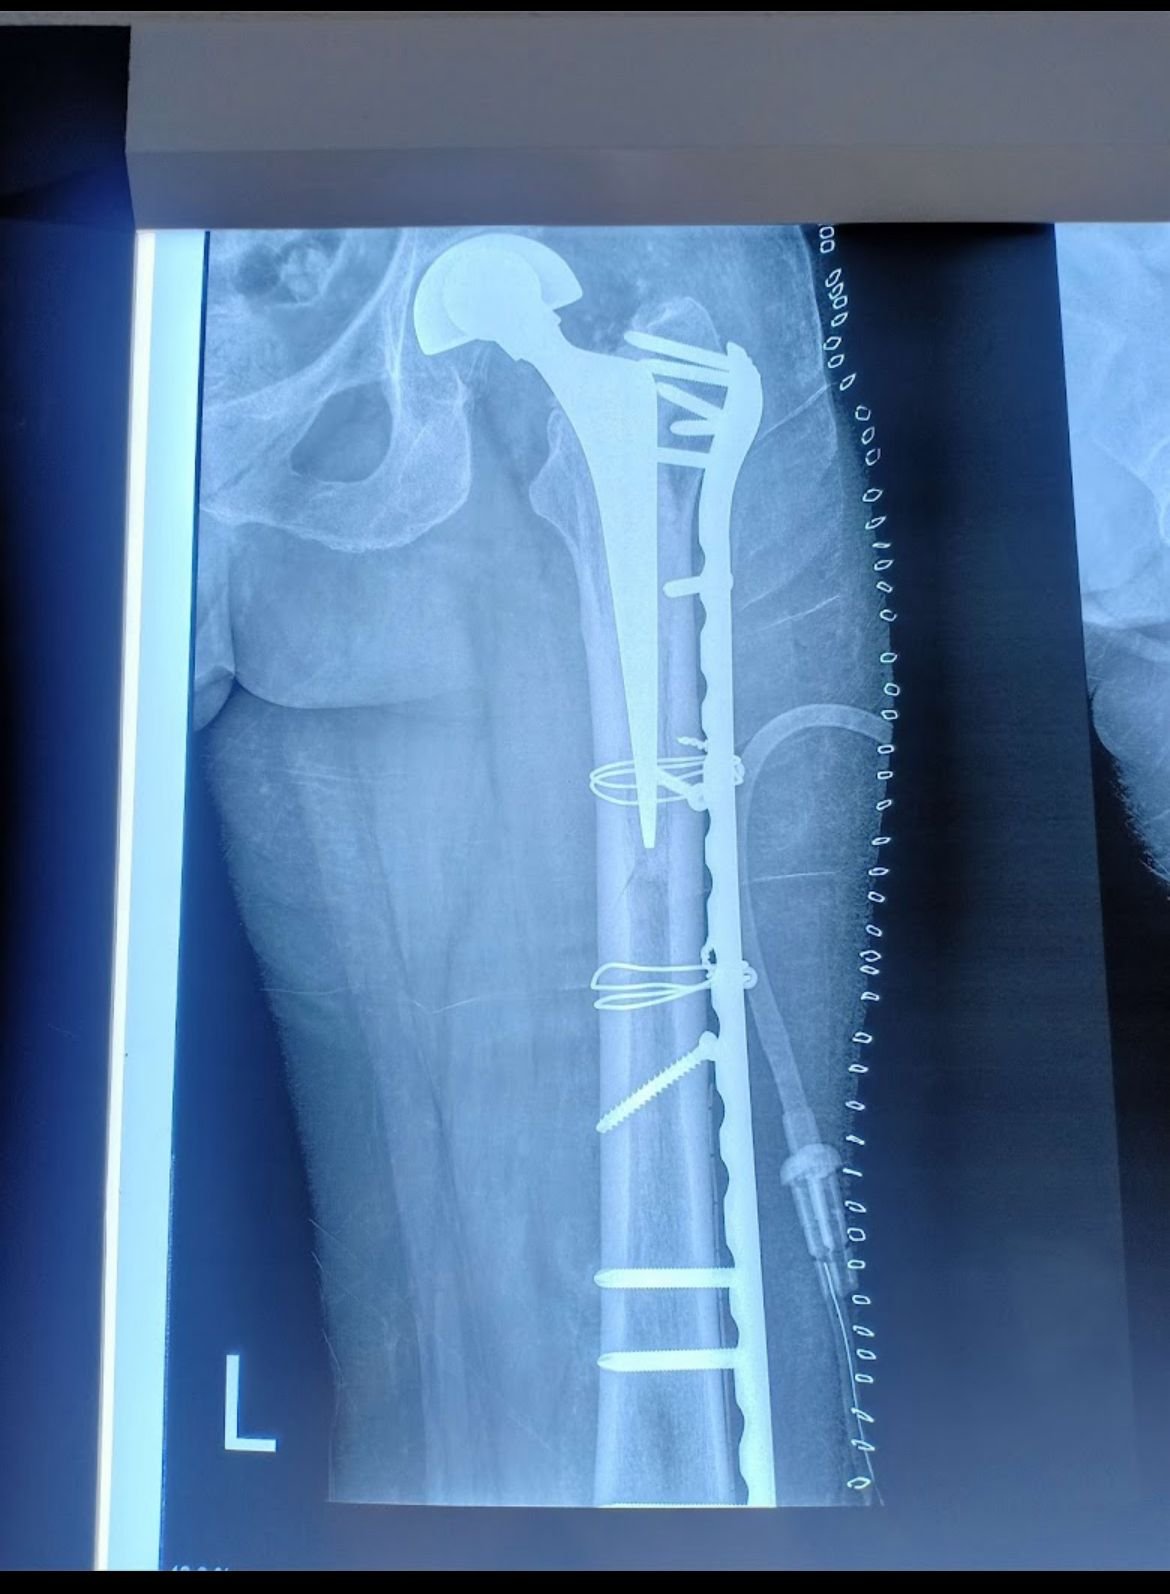

Hip Replacement

Gallery